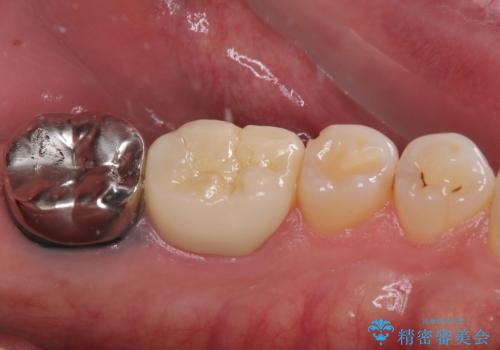

根管治療を行った奥歯は、再発防止や残された歯質を守るため、クラウンによる補綴治療が必要となります。